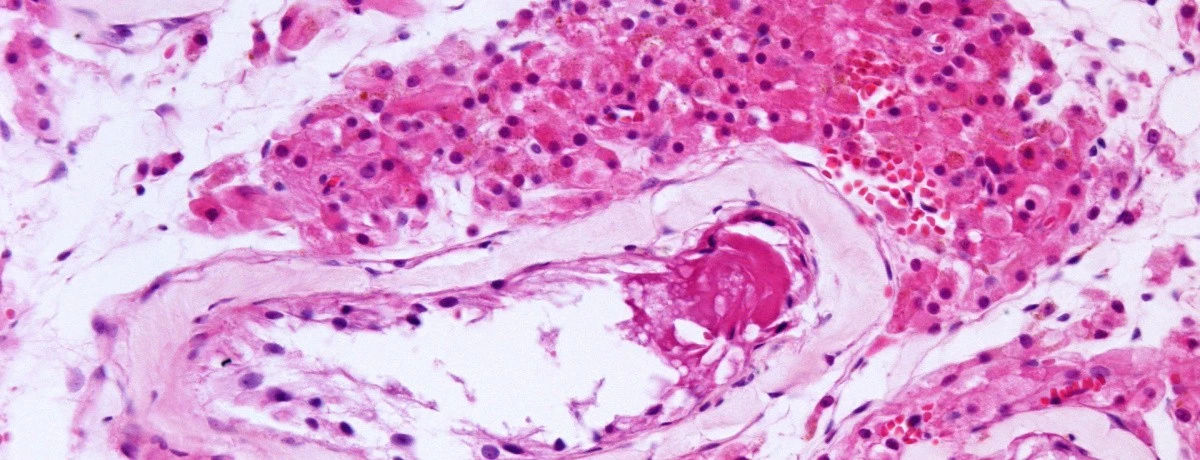

↑ topIl termine atrofia testicolare indica una condizione per cui uno o entrambi i testicoli sono di dimensioni ridotte.

L’atrofia testicolare è permanente e indipendente dalle condizioni del momento, è può essere causata da diversi fattori di natura traumatica, patologica o anche farmacologico-chimica.